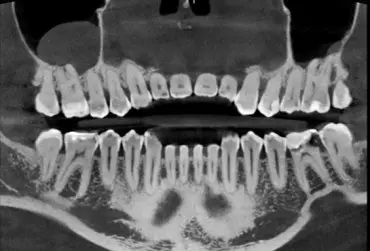

Artefakty metalowe w obrazowaniu stomatologicznym niejednokrotnie stanowią bardzo poważne wyzwanie dla dokładnej diagnostyki i planowania leczenia. Ich występowanie wynika przede wszystkim z obecności metalowych uzupełnień, implantów i aparatów ortodontycznych, co komplikuje interpretację obrazów 3D. Niestety, materiały takie jak gutaperka również powodują występowanie rozbłysków, które bez ich redukcji praktycznie uniemożliwiają trafną diagnozę. W tym artykule omówiono przyczyny powstawania artefaktów metalowych, dokonano przeglądu aktualnych metod ich redukcji oraz omówiono najnowsze technologie w tym zakresie.